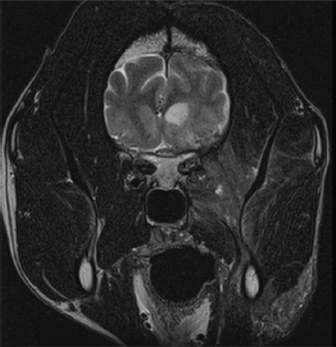

The dog was anesthetized for an MRI of the head with T1-weighted (T1W), T2-weighted (T2W), gradient echo (GRE), fluid-attenuated inversion recovery (FLAIR), and T1W post gadodiamide (Omniscan, GE Healthcare AS, Oslo, Norway) (50 mg/kg) contrast sequences. Findings included a marked patchy hyperintensity (T1W, T2W, and FLAIR) of the right-sided soft-tissue structures of the head with marked heterogeneous contrast enhancement rostral to the right eye extending caudally to the level of the temporomandibular joint and ventrally to the level of the mandible. Marked right-sided meningeal enhancement extended to the occipital and frontal lobes. Ill-defined T2W and FLAIR hyperintense and T1W hypointense contrast-enhancing regions were present in the right piriform and temporal lobes. Concurrently, there was a marked mass effect causing deviation of the falx cerebri to the left and compression of the right lateral ventricle. In addition, there were T2W and FLAIR hyperintense and non contrast-enhancing regions in the right caudate nucleus (Fig. 2). A cerebellomedullary cisternal cerebrospinal fluid (CSF) sample was obtained. Cell count analysis was within normal limits. A differential cell count revealed the presence of increased numbers of nondegenerate neutrophils (31%) and eosinophils (8%). There was a moderate increase in microprotein (CSF microprotein concentration 63 mg/dl [rr < 25 mg/dl]). No fungal structures were identified on a GMS stain of a concentrated preparation of CSF. The owner elected humane euthanasia.

Fig. 2. Representative axial T2-weighted MRI image demonstrates patchy hyperintensity of the soft tissues of the right side of the head with heterogeneous contrast enhancement extending ventrally to the level of the mandible. The right-sided meningeal enhancement is present. Ill-defined hyperintense regions in the right temporal lobe display marked mass effect causing deviation of the falx cerebri to the left and compression of the right lateral ventricle.